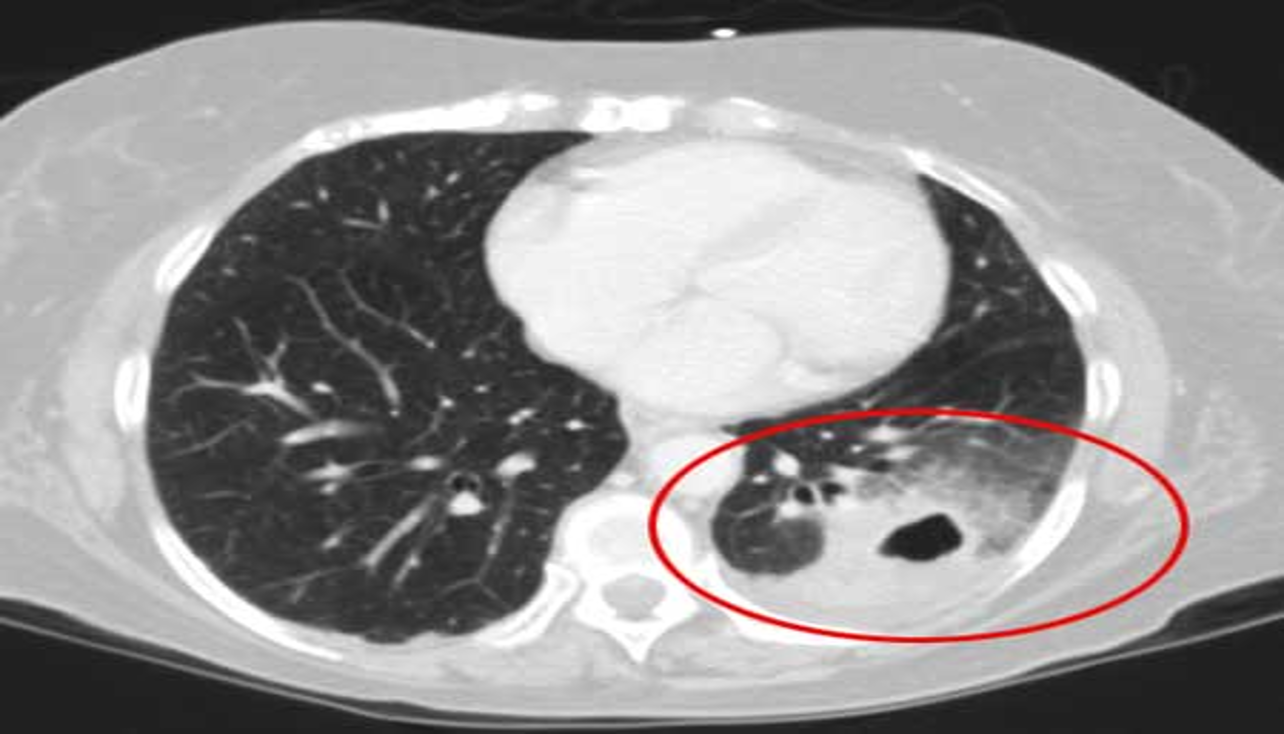

CT scan:

Provides more detailed imaging of suspected abscess or empyema.

RT. lower lobe; Lobar pneumonia: Opacity of one or more pulmonary lobes & Presence of air bronchograms

- Spine blackness increased reversibly (Spine sign); lower part opaque

CT chest (axial plane; lung window) of a patient with a history of bacterial pneumonia

Opacification of much of the right lower lobe parenchyma is the result of air space consolidation. Pulmonary vessels are obscured and patent airways

(air bronchograms, white dashed line) are seen.